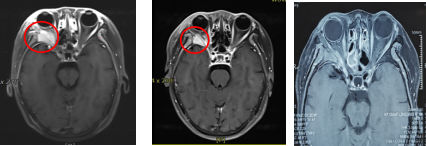

Case 1: Female, 44 years old, squamous carcinoma of the right lacrimal sac. She visited our hospital in July 2022, and on examination, she was found to have a swelling of about 3 cm × 4 cm in size in the lower eyelid of her right eye, with mild limitation of eye movement in all directions. After a thorough examination and evaluation of the patient, the patient was treated on 20 July 2022 with CIRT. The prescribed dose for the first course: PTV 40Gy (RBE)/10fx; lateral position, 2D homogeneous scanning, and the dose distribution is shown in Figure 1A.The prescribed dose for the second course: PTVboost 24Gy (RBE)/6fx; supine position, 2D homogeneous scanning. The total dose to the tumour area was 64 Gy (RBE)/16 F, 4.0 Gy (RBE)/F, and 5 F/w, and the dose distribution is shown in Fig. 1B.Comparison of the dose distribution of axial images between CIRT and volume-modulated intensity-adjusted radiotherapy (VMAT) plans while both fulfilling the prescriptive requirements, and the range of the surrounding normal tissues irradiated at low doses was significantly smaller for the CIRT plan compared to the VMAT plan, see Fig. 2A and The efficacy of CIRT was compared by imaging data before and after treatment, and the patient's efficacy was assessed according to the Response to Evaluation Criteria for the Evaluation of Solid Tumours (RECIST) 1.1, and the efficacy of treatment reached a complete remission (CR) 3 months after treatment, as shown in Fig. 3. During the CIRT treatment period and in the first month after the treatment, the patient developed grade 1 acute radiation conjunctival injury; 3 months after the end of radiotherapy, she developed dry eyes, and the use of eye drops for a long time was considered to be grade 1 radiation conjunctival damage, which was considered to be grade 1 radiation conjunctival damage. , considered grade 1 radiation conjunctival injury (RTOG Acute Radiation Injury Grades), no late adverse events greater than grade 2 were observed.Combination of a target (cetuximab) during CIRT treatment, with disseminated rash on the face during the treatment period, grade 1 on the Common Terminology Evaluation Criteria for Adverse Events. As of September 2024, the patient is currently disease-free and continues to be followed for the long term.

Figure 3 Comparison of magnetic resonance imaging (MRI) and physical signs in patients with dacryocystosquamous cell carcinoma before and after CIRT treatment

Note: Figure 3A: MRI examination before CIRT treatment showed that: the right lacrimal sac was occupied, the boundary between the eyeball, the medial rectus muscle and the inferior rectus muscle was not clear, the eyeball was compressed and displaced, and the right nasolacrimal duct was invaded. Figure 3B: Abnormal signs before CIRT treatment; Figure 3C: MRI examination after CIRT treatment showed that: the lesion disappeared, and the efficacy evaluation was CR; Figure 3D: Recovery of physical signs after CIRT treatment.